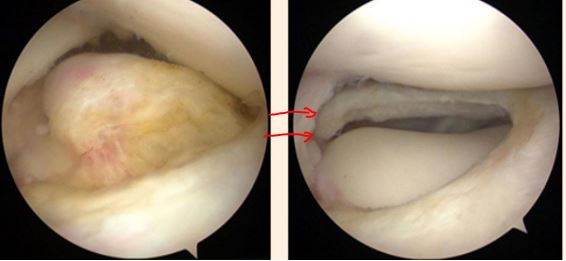

1,女性,14 岁,右膝关节弹响,膝关节交锁。关节镜下见外侧完全盘状半月板 ,予关节镜下成形术!

半月板为盘状,大而厚,完全覆盖胫骨平台

使用蓝钳等关节镜器械,修整半月板,切除中央部

盘状半月板成形后为正常的“半月”形